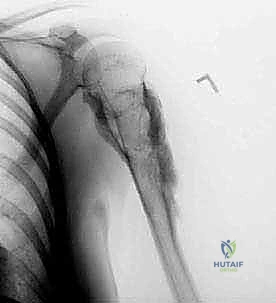

* Plain Radiographs (AP, lateral, axillary views): These were our initial diagnostic tools, providing crucial clues to the nature of the neoplasm – note the bone expansion and cortical thickening characteristic of chondrosarcoma.

Figure 3: Preoperative AP and lateral radiographs of the proximal humerus showing a chondrosarcoma.